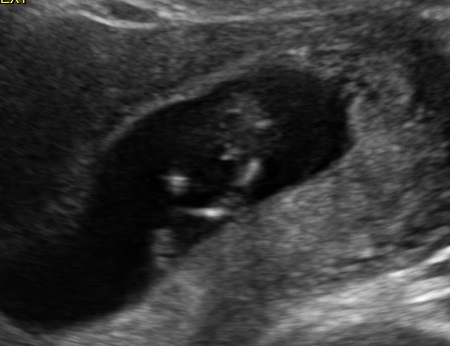

I was 11w5d when I had the scan, although I was measuring 12w1d. I know it's still pretty early, but am wondering if you see anything on these (terrible quality) scan pics! Attachment 23572Attachment 23571Attachment 23573Attachment 23574Attachment 23575